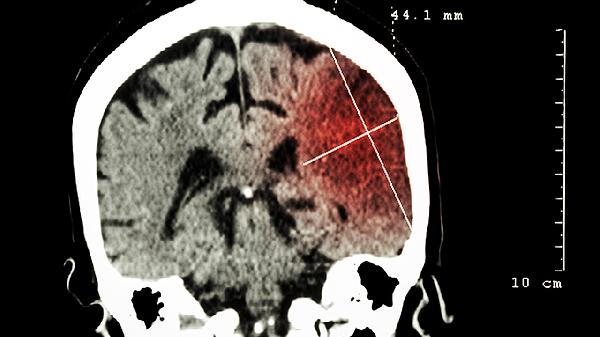

脑安滴丸适用于脑血栓形成的急性期,能够帮助改善局部血液循环。脑血栓可能与动脉粥样硬化、血液黏稠度过高等因素有关,通常表现为突发性偏瘫、言语不清等症状。患者在医生指导下可配合使用阿司匹林肠溶片、氯吡格雷片等抗血小板药物。

脑安滴丸可用于脑梗死恢复期的治疗,有助于促进神经功能康复。脑梗死恢复期可能与侧支循环建立不全、脑组织缺血再灌注损伤有关,常遗留肢体麻木、肌力减退等症状。建议联合康复训练,并遵医嘱使用胞磷胆碱钠胶囊、奥拉西坦胶囊等神经保护剂。

该药对脑梗死后遗症期的肢体功能障碍有一定辅助治疗作用。后遗症可能与神经细胞不可逆损伤相关,表现为持续性运动障碍、认知功能下降等。可配合针灸治疗,必要时遵医嘱使用长春西汀片、尼莫地平片等改善脑代谢药物。